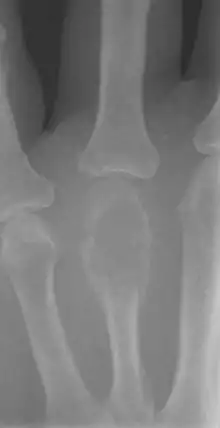

Diagnostic radiologic

Aspectul radiologic al TCG este caracteristic. Practic, semnele clinice și radiologice permit adesea punerea diagnosticului de TCG înaintea biopsiei.

Caracteristici radiologice:

- tumoră radiotransparentă în totalitate. Tumora are proprietăți intens osteolitice. Crește relativ încet, circular, în toate direcțiile, forma tumorii fiind rotund-ovalară. Osteoliza este omogenă și nu conține nici calcificări și nici osificări.

- tumora este situată excentric în os, în regiunea metafizo-epifizară. Afectează deopotrivă osul spongios și osul cortical. Limitele tumorii cu osul spongios sunt regulate și clar definite sau doar ușor estompate.

- TCG este lipsită de o scleroză osoasă periferică densă. Mineralizarea tumorii primare este rară. Dar atunci când TCG se întinde în țesuturile moi vecine (metastază sau recurență locală), pe radiografie apar de obicei calificări periferice.

Din cauza reacției osteogenice reduse de la periferia tumorii, este lesne de înțeles de ce TCG este rareori compartimentată radiologic.

- tumora invadează întreaga metafiză și epifiză pe măsură ce crește, osul este expandat progresiv, corticala este roasă neuniform și tumora protruzionează în părțile moi, lipsită de orice delimitare vizibilă radiologic.

- tumora dezvoltată spre cartilajul articular poate trece dincolo de el, în articulație, aspect important în alegerea tehnicii chirurgicale.

Campanacci a propus o clasificare radiologică a gradului de agresiune a TCG în 3 categorii ce corespund stadiilor Enneking pentru tumorile benigne:

1) TCG gradul 1: sunt tumorile "calme" sau "latente", cu corticala intactă și margini bine definite. Corticala nu este lărgită. Osteoliza este bine delimitată și marcată de o ramă de ușoară hiperostoză peritumorală. Tumora nu este foarte mare și nu atinge cartilajul articular. Această varietate este cea mai rară.

2) TCG gradul 2: sunt tumorile "active". Marginile tumorii sunt încă bine delimitate dar mai puțin nete, mai neclare. Ele nu mai sunt radioopace. Corticala este mult subțiată dar tumora rămâne mărginită clar de periost. Corticala poate fi expandată. Adesea tumora este foarte aproape de cartilajul articular sau chiar îl atinge (prodund). Este gradul de TCG cel mai frecvent întâlnit și cel mai caracteristic.

3) TCG gradul 3: sunt tumorile "agresive". Tumora are margini nedefinite și corticala distrusă, cu dezvoltarea ei în afara osului, în părțile moi. Tumora este o masă globuloasă radiotransparentă. Nu are deloc o delimitare radioopacă. Când se fac radiografii succesive, este observată lărgirea rapidă a tumorii, ceea ce sugerează agresivitatea ei. Tumora distruge cea mai mare parte sau chiar toată epifiza și întotdeauna atinge cartilajul articular. Acest tip de tumoră este rar.